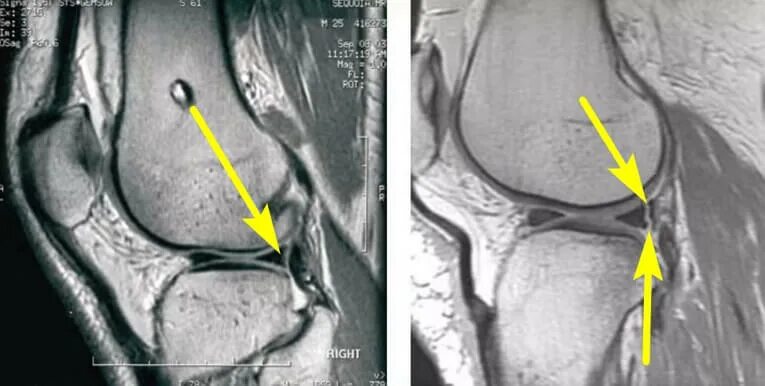

Дегенеративное изменение мениска 1 степени по stoller